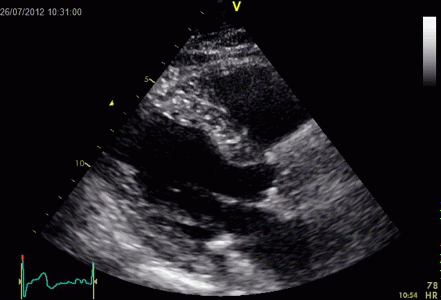

İKİNCİ DÜZEY (İLERİ DÜZEY) ULTRASONOGRAFİ

Ayrıntılı ultrasonografi veya detaylı ultrasonografi veya ileri düzey (ikinci düzey) ultrasonografi aynı anlamdadır.